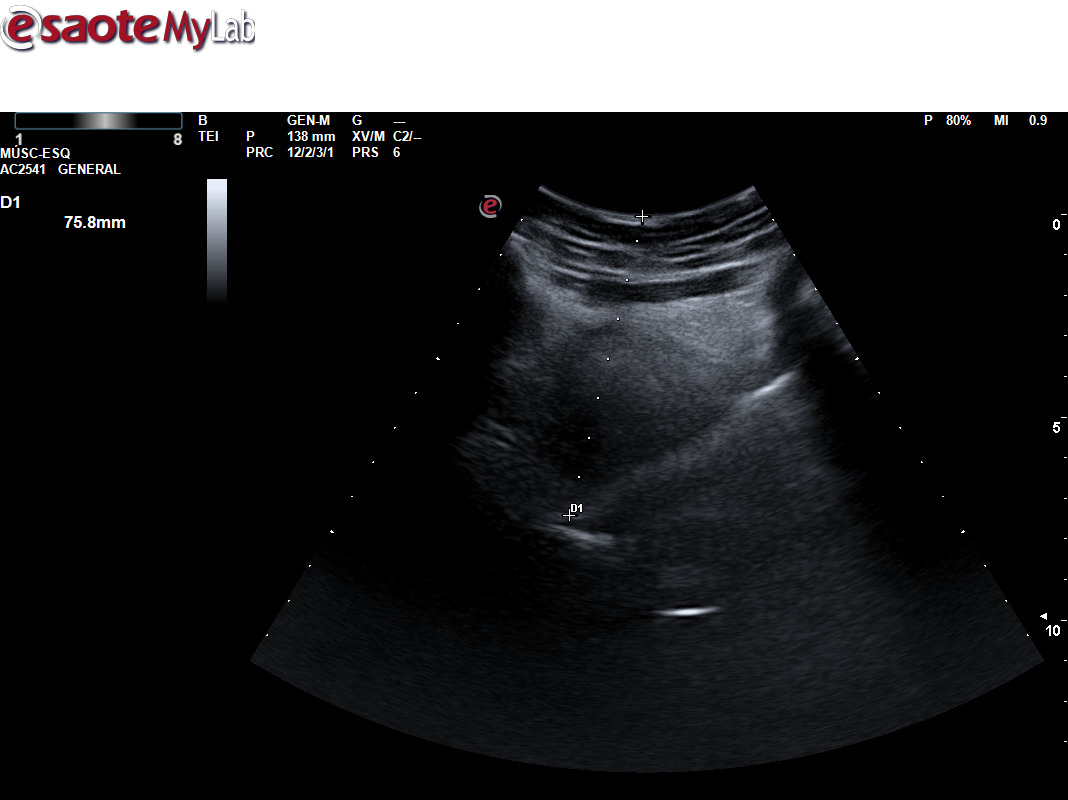

Para ello ponemos en práctica el protocolo específico de detección ecográfica de AOS, mediante la medición de la base de lengua y del espacio retrofaríngeo posterior para ver si cumple los criterios ecográficos establecidos, con las mediciones correspondientes que establecen la sospecha.